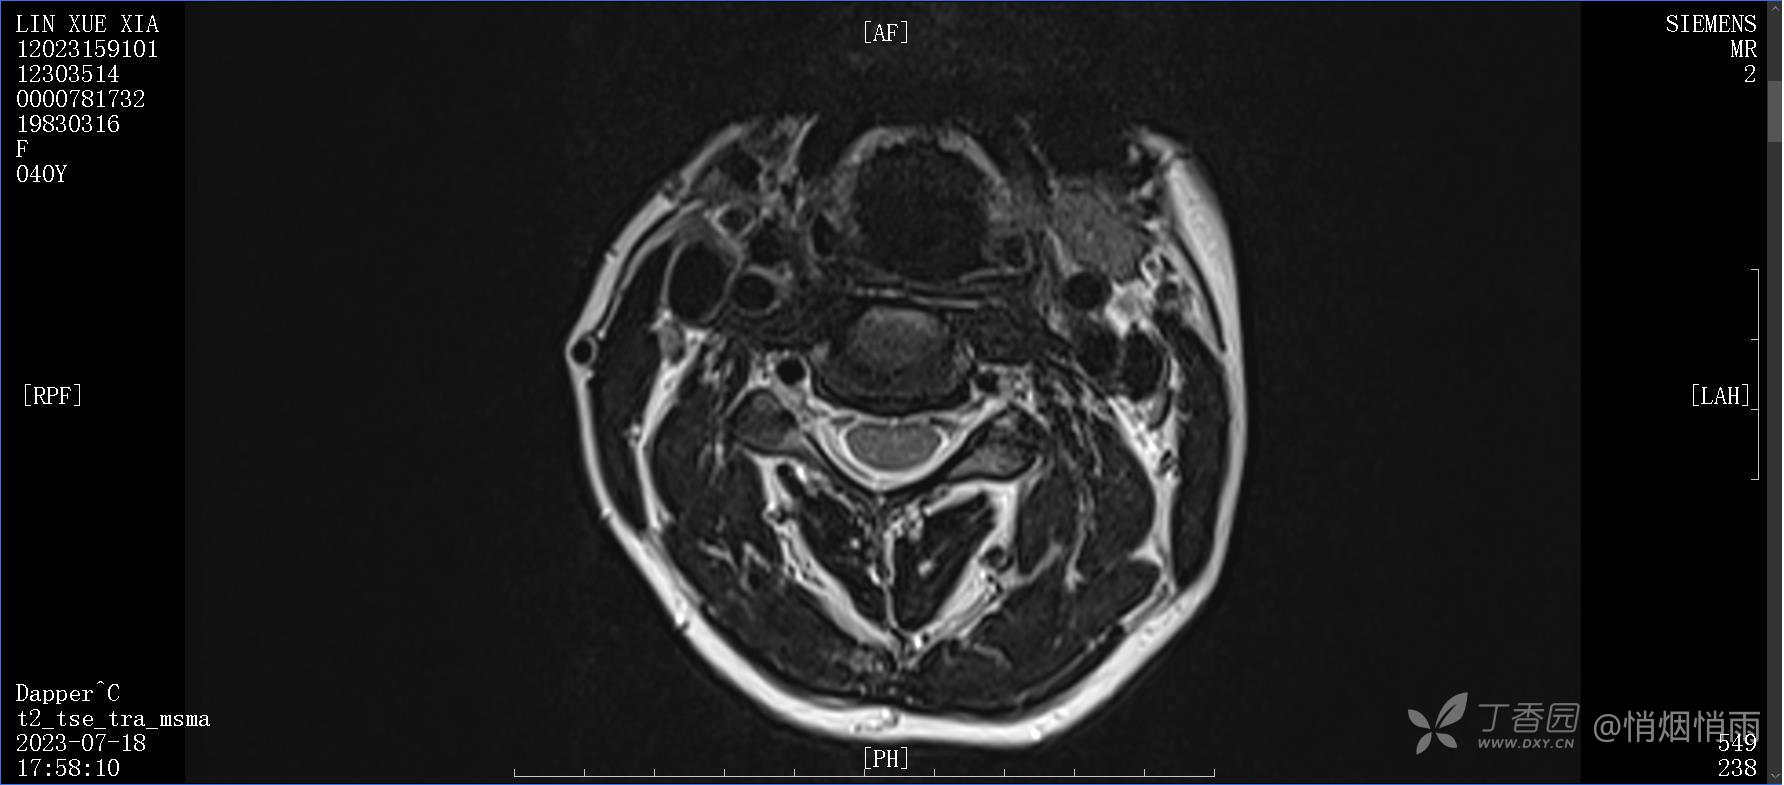

NeurothinkerZ 推荐患者女性,40岁,因右肩背部疼痛班活动受限4日余入院(2023-07-17)。

病史:入院前4天无明显诱因突然感右肩背疼痛伴随活动受限,自行口服依托考昔、艾瑞昔布等药物治疗,院外应用肩关节局部手法按摩等,均无明显改善。外院门诊诊为颈椎病。自诉既往多次“胸椎小关节紊乱”于当地诊所行手法按摩,治疗后好转,否认慢性疾病病史、外伤史、手术史,诉青霉素过敏,无其他药物食物过敏史,否认吸烟史、饮酒史,月经正常,经量正常。

目前的诊断,暂时依据辅助检查诊为肩袖损伤,但是患者疼痛的性质和特点,却不是单纯的肩袖损伤所致。考虑过胸廓出口综合征,但是该疾病会出现肩胛区的疼痛吗?(由于考虑到费用的问题,没再进行下一步的检查)带状疱疹会有如此的症状吗?